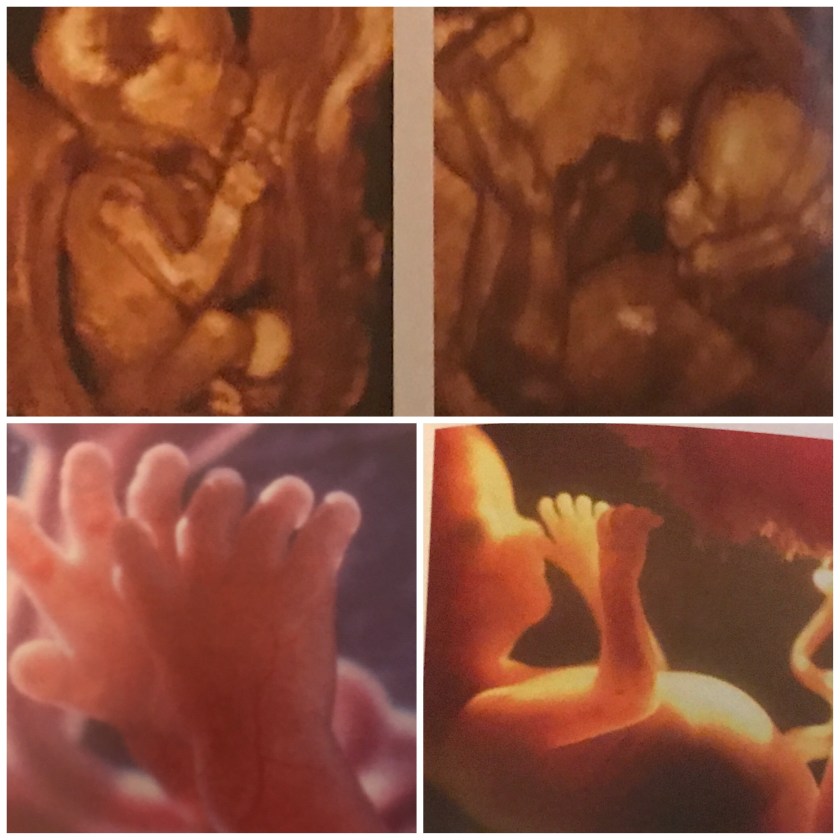

This week is characterized by a lot of movement as our baby can and does move arms and legs at will bending, stretching, kicking and punching. While too early for me to feel this as kicks and lunches, I did feel a lot more of the gurgling movement that I’d expect. Baby also begins sucking his or her thumb more frequently.